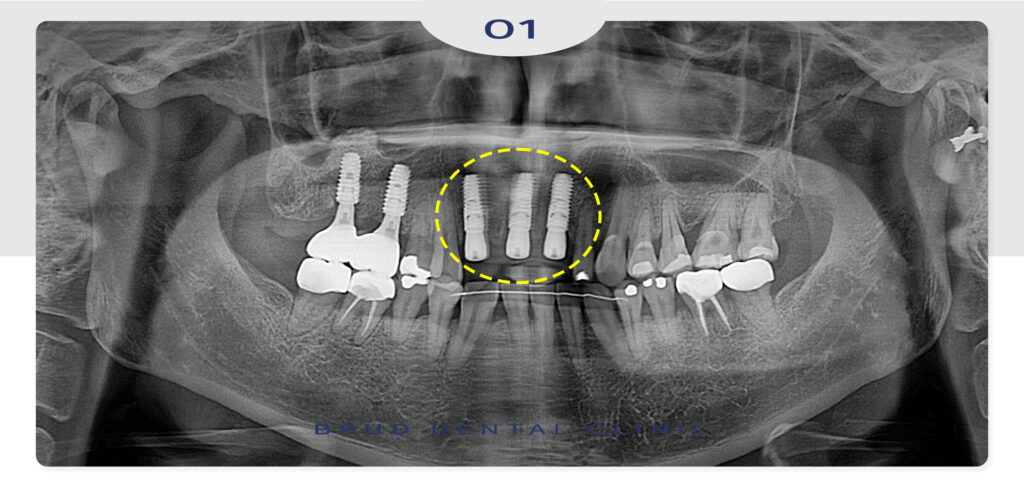

24.08.30

많은 양의 뼈이식을 동반하여 최종 보철물까지

문제 없이 마무리를 하였는데요.

25.07.10

어금니 치료를 마치고 난 뒤,

위쪽 앞니의 치근단 병소로 인해

잇몸에 누공이 형성되어 있는 상태로

재내원 해주셨는데요.

자연치를 살려쓰실 수 있는 치근단 절제술 상담을

진행해 보았으나, 보철 교체와 더불어 예후가

좋지 않을 것으로 판단되어 앞니 세개를 발치하고

옆쪽 치아의 크라운까지 진행하기로 계획하였습니다.